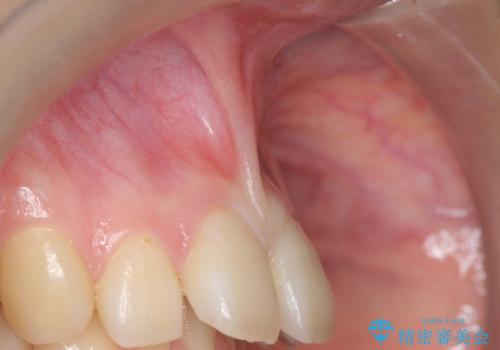

上顎前歯の隙間と出っ歯の一因は上唇小帯と呼ばれる上唇と歯茎を結ぶ線維性の付着によるものであり、矯正を行っても後戻りのリスクが高いことから、矯正前に上唇小帯の切除を行いました。

上唇小帯とは上唇と歯茎を結ぶ線維性の付着のことです。上唇小帯の付着位置が前歯に近いと今回のケースのように正中離開(前歯の隙間)の原因となります。